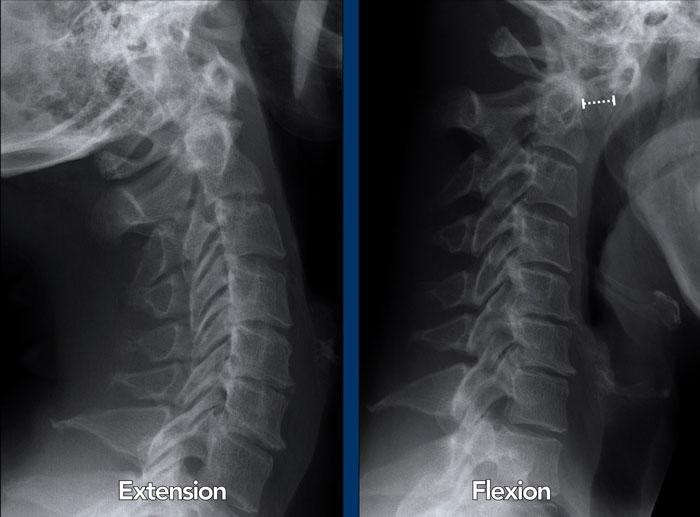

Trật khớp đội – trục

Cột sống cổ thường bị ảnh hưởng trong viêm khớp dạng thấp và có thể biểu hiện dưới dạng mất vững khớp đội – trục, trật khớp dưới trục hoặc lồng nền sọ kèm theo sụt lún sọ não.

Sụt lún sọ não xảy ra khi mỏm răng xâm lấn vào lỗ chẩm.

Trật khớp đội – trục là một biến chứng quan trọng và có thể đe dọa tính mạng của viêm khớp dạng thấp. Tình trạng này được xác định khi khoảng cách giữa mỏm răng C2 và cung đốt đội vượt quá 3 mm. Nguyên nhân là do lỏng lẻo dây chằng do viêm.

Mất vững tại khớp này có thể gây ra nhiều triệu chứng thần kinh do chèn ép tủy sống.

Hình ảnh

Khi cúi cổ, khoảng cách giữa mỏm răng và mặt sau cung trước đốt đội bị giãn rộng (14 mm) (bình thường ≤3 mm).